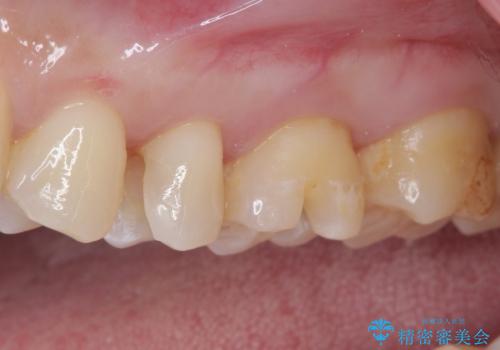

そして次の来院時、セラミックインレーを装着し、噛み合わせなどの調整を行います。

自然な色調で大変満足されました。